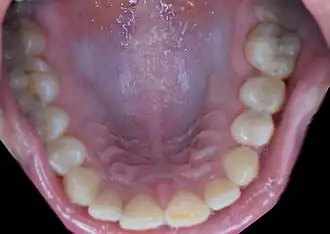

Rugae folds behind the anterior teeth in the hard palate of the mouth